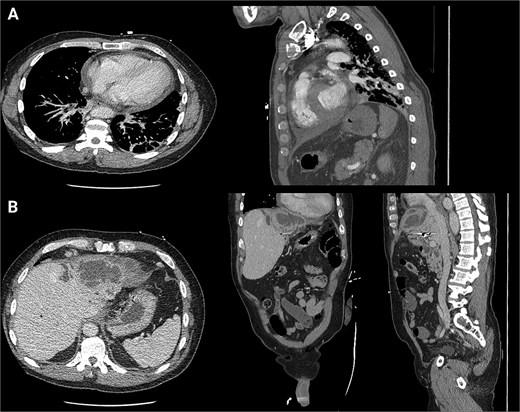

A 62-year-old male presented with the chief complaints of fevers, fatigue, and body aches for one week. He reports an ostomy placed fifteen years prior to, “drain the rocks from my liver.” He reports that stones drained from the ostomy for two years after it was placed. Physical exam was notable for abdominal incisions and left upper quadrant ostomy. Initial workup found a WBC count of 14 000×103/μl, alkaline phosphatase of 571 U/L, and normal bilirubin. Given his vague abdominal pain and fevers, a contrasted computed tomography (CT) scan of the abdomen was performed. This confirmed that the ostomy was a conduit from the biliary tree to the skin. It additionally found a 6.6 × 6.4 cm intrahepatic abscess (Fig. 1). He was admitted and was started on IV antibiotics. Gastroenterology (GI) and Interventional Radiology (IR) were consulted for endoscopic or image-guided drainage, but these were deferred given the tortuosity of his conduit and lack of a safe window, respectively. Given he had improved on antibiotics, it was deemed that operative intervention was not indicated at that time. He was transitioned to oral antibiotics, scheduled for outpatient endoscopic retrograde cholangiopancreatography (ERCP) to better delineate the biliary anatomy, and discharged. Of note, this institution’s policy is that Advanced Endoscopists perform ERCPs. At this time, there are no surgeons who performed ERCPs.

Initial CT scans. (A) Axial images progressing from superior to inferior. These show the hepatic abscess as well as the small bowel limb anastomosed to the biliary tree. (B) The same scan, but in a coronal view. (C) The same scan, but from a sagittal view. This view again illustrates the limb of a small bowel anastomosed to the biliary tree. Surgical clips are seen in the gall bladder bed.